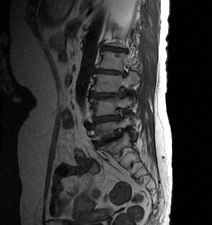

척추관협착증 이미지

진단은 방선 소견으로 주로 확인되는데 평면 사진으로 척추간 간격을 확인할 수 있고, 동적 촬영으로 불안정성 확인을 할 수 있는 단순 방사선 촬영, 눌린 부위를 나타낼 수 있는 척추강조영술, 척추관의 골조직의 크기와 모양을 정확히 알 수 있고 신경관도 관찰 할 수 있으며 전산화 단층 촬영술, 그리고 골조직외에 연부조직 사이의 상태까지 잘 알 수 있는 자기공명영상(MRI)등을 이용할 수 있습니다.

MRI는 뼈와 신경, 디스크를 완전히 구분하여 보여주어 목 디스크의 진단을 더욱 세밀하고 쉽게 할 수 있습니다.